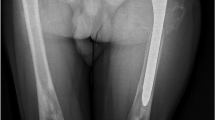

EFD describes a distinct abnormality of remodelling of the metaphyseal-diaphyseal areas with a progressive enlargement of the metaphyseal area, due to local bone marrow infiltration by Gaucher cells [31]. This leads to a lack of the typical concave di-metaphyseal curve resulting in an Erlenmeyer flask-like appearance. The sites affected are: the distal femora, occasionally also within the metaphyseal region of other tubular bones, and the proximal tibia or humerus. These changes occur before puberty, after which the bone alteration develops progressively. Modeling deformities, particularly the EFD in the distal femur, are often-described (30–45 % of adults) (Fig. 1), although they appear to be asymptomatic and not pathognomonic for GD. There is no relationship between this radiologic finding and other skeletal complications of GD [31].

Bone infarcts may be caused by infiltration of Gaucher cells leading to alterations of vascularity and additional inflammatory processes [24]. Bone pain may be related to the pathologic processes evident by radiography, magnetic resonance imaging (MRI), and computed tomography, or have the character of a “crisis” which is a self-limiting, albeit exquisitely painful event, associated with signs of acute local and/or systemic inflammation. Bone crisis is an independent predictor for future osteonecrosis; during pregnancy the risk is increased [36]. Bone infarcts may occur with no clinical symptoms, or slight pain, or sudden onset of severe localized pain which may be the first feature of osteonecrosis. Bone crisis is typically but not necessarily associated with local tenderness, erythema, and swelling, and it may be accompanied by fever, elevated white blood cell count, and an accelerated erythrocyte sedimentation rate [33]. The debilitation may last a few days, usually requiring immobilization of the affected area and narcotics for pain relief and hydration. Spontaneous bacterial osteomyelitis is rare in GD, and the differentiation between aseptic (“bone crisis”) and pyogenic osteomyelitis is difficult or even impossible at the time of onset if this is the presenting manifestation of GD. The only way to avoid misdiagnosis is when the physician is aware of GD and looks for other disease features such as splenomegaly or thrombocytopenia. Otherwise, negative blood cultures and sterile aspirates are used to exclude pyogenic osteomyelitis [24]. Bone infarcts are often followed by necrosis and fractures [36]. Osteonecrosis, also known as AVN, and episodes of bone infarction are the most relevant and invalidating skeletal manifestation. Osteonecrosis is irreversible and predominantly affects the femoral heads (Figs. 2, 3), knees or proximal humerus, and less commonly the vertebral bodies. Osteonecrosis will typically lead to joint collapse with consequent pain, disability, and a poor quality of life [12, 24]. This devastating feature was more common in the pre-ERT era, particularly after splenectomy, and usually occurred in teenagers and young adults. Mistry et al. [37] have explored the link between osteonecrosis and the interval between diagnosis and initiation of specific treatment. The authors have demonstrated that the risk of AVN was increased if the initiating of treatment occurred 2 years or more after diagnosis had been made. This study also confirmed that the higher risk of AVN was among splenectomized patients [37].

Orthopedic surgery has an important role for patients who have developed irreversible joint damage (osteonecrosis) before the availability of ERT and, infrequently, despite ERT [64]. In case of femoral head osteonecrosis, total hip arthroplasty eliminates pain, preserves ambulation, and should allow for satisfactory daily life. In the future, newer types of implants would allow longer revision-free periods [64]. Lebel et al. have assessed the correlation of patient demographics, including ERT with bone histology, to facilitate decisions of whether and when to perform hip replacement surgery in patients with GD [65]. The histology of surgically removed femoral heads and categorized findings according the presence or extent of osteonecrosis, Gaucher cell infiltration, and bone regeneration qualifiers using a tripartite histology-based scoring system, have been examined. Histologic findings of Gaucher cell infiltration and bone regeneration qualifiers did not correlate with demographics or with exposure to ERT, and most specimens unexpectedly showed good regenerative response to osteonecrosis despite heavy Gaucher cell infiltration.